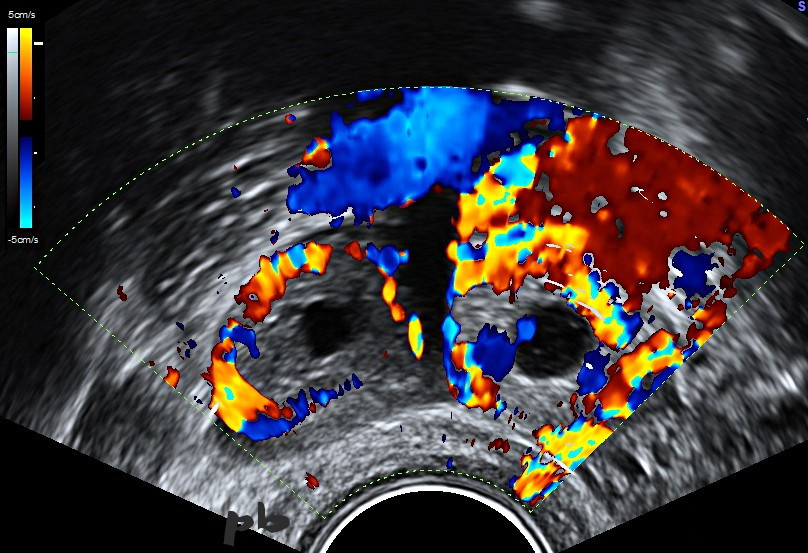

21-Ectopic pregnancy (same patient as 20)

Gestational sac and corpus luteum side by side.

Vascular ring around both images. Doppler does not allow for differential diagnosis.